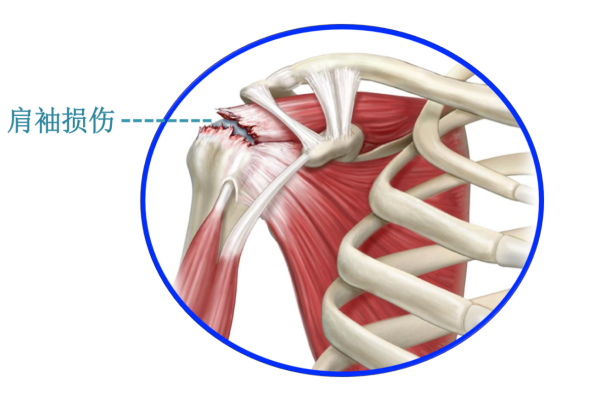

肩袖是肩關節周(zhōu)圍的一組肌(jī)腱,如同“袖口”般包裹(guǒ)住肩關節,主要對肩關節(jiē)起(qǐ)到(dào)旋內、旋(xuán)外和(hé)外展動作。